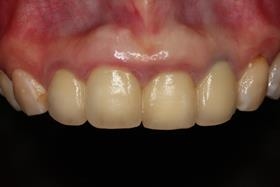

治療前,X光片及口內照片。

假牙完成後,植牙與自然牙,真假難辨;病患恢復自信的笑容。